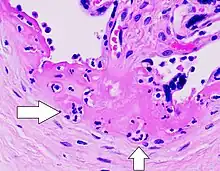

| Gross pathology of severe intervillositis, with dark red and soggy tissue. | |

Chronic histiocytic intervillositis

Chronic Histiocytic Intervillositis (CHI or CHIV) also known as Chronic Intervillositis of Unknown (A)etiology (CIUE) and Massive Chronic Intervillositis (MCI) is defined as a diffuse infiltration of mononuclear cells (histiocytes, lymphocytes, monocytes) of maternal origin into the intervillous space within the placenta. It often results in severe intrauterine growth restriction which can lead to miscarriage or stillbirth. Overall perinatal mortality rate is high: 41%[6] to 77%.[7] Recurrence rate is also high: 67%[7] to 100%.[6]